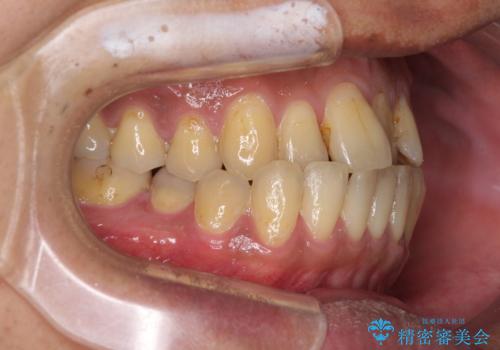

前歯のクロスバイトを改善 ワイヤー装置での非抜歯矯正

- 骨格的な咬み合わせのズレ、前歯のデコボコとクロスバイトを気にして来院された患者様です。

骨格のズレが顕著であると診断され、マウスピース矯正では奥歯の咬み合わせが整えにくいと判断し、ワイヤー装置による矯正治療を行うこととしました。

上下の叢生は速やかに改善できましたが、右側のクロスバイトの改善に1年以上の期間を要しました。